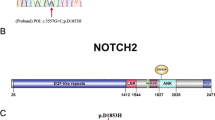

A total of 26.99 million raw reads were produced by sequencing, and over 96% of the sequenced bases possessed a quality score of Q20. The raw sequencing data generated more than 5000 Mb of effective data and the average sequencing depth on target areas was over 90×. In total, 1419 SNPs and 362 indels, including 1398 SNPs and 274 indels in the exonic regions, and 93 SNPs and 88 indels in splicing sites, were obtained. For the identified SNPs and indels, the synonymous variants and common variants (MAF > 0.01) deposited in the dbSNP147, 1000 Genomes Project and ExAC databases, were excluded. For the remaining nonsynonymous variants, we evaluated their potential pathogenicities with a combination of the SIFT, PolyPhen-2 and MutationTaster prediction programs. Based on these filtering criteria, a novel heterozygous missense variant in the exon 4 in the ESR1 gene (NM_001291230.1), c.619G > A (p.A207T), was identified. The identified ESR1 variant was validated by direct Sanger sequencing of the patient sample (Fig. 2A). This novel variant was not identified in 364 unrelated female controls without PCOS, or in the ExAC database and 1000 Genomes Project databases.

Evolutionary conservation analysis and protein structural modelling of the ESR1 (p.A207T) mutatiom. A Representative sequencing electropherogram of the ESR1 (p.A207T) mutation. The arrow indicates the location of the mutation. B Evolutionary conservation analysis of the ESR1 (p.A207T) mutation. Sequence alignment with other species indicates that the affected Ala (A) 207 residue is highly conserved in all 18 vertebrate species. C Structural difference between wild type ESR1 (p.A207) and mutated ESR1 (p.T207) proteins. The protein structures of wild type and mutated ESR1 proteins were modelled based on the crystal model of the human ESR1 protein. D Location of ESR1 missense mutations found in clinical samples. The A207 residue (red text) shows the novel mutation identified in our study. AF1, activation function 1; DBD, DNA binding domain; AF2, activation function 2; LBD, ligand binding domain

Evolutionary conservation analysis and protein structural modelling

Evolutionary conservation analysis based on 18 vertebrate species, from Homo sapiens to Xenopus tropicalis, showed that the ESR1 A207T mutation changed a highly conserved alanine to threonine at the 207th residue (Fig. 2B). The results of protein structural prediction showed that the ESR1 A207T mutation caused marked structural change when compared with its wild-type counterpart (Fig. 2C). The location of all of the reported ESR1 missense germline mutations in prior studies [13,14,15] and somatic mutations in clinical samples from the Catalogue of Somatic Mutations in Cancer (COSMIC) database (https://cancer.sanger.ac.uk/cosmic); among these mutations, A207T is located in the DNA binding domain (DBD) (Fig. 2D).